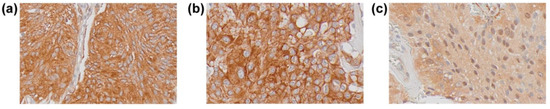

3.2. Immunohistochemical Expression of SSTRs in Meningiomas